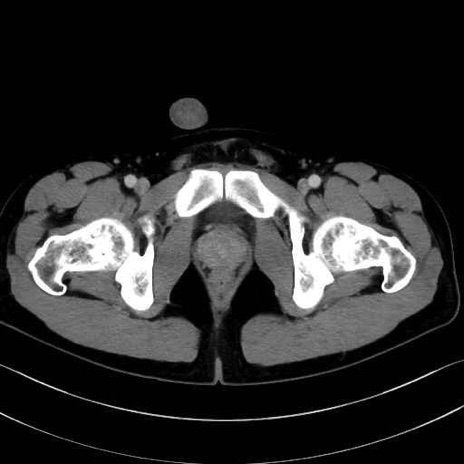

外側広筋(vastus lateralis) のCT画像の解剖

外側広筋 (Vastus lateralis)